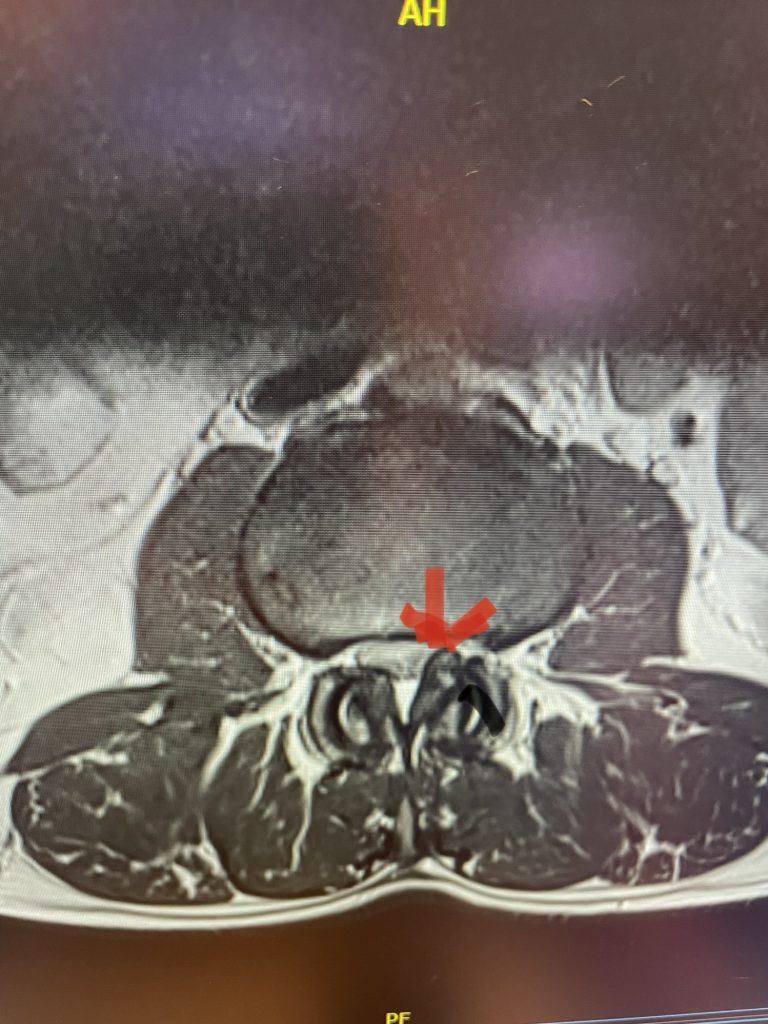

The spinal synovial cyst is one of the most interesting expressions of spinal instability. They emanate from the synovial lining of a degenerated facet joint that […]

People are obsessed with cysts! When you think about it, the body likes to form cysts. Why does this happen? Cysts can form just about anywhere […]

Nervous tissue is soft. The thecal sac is surrounded by a rigid bony ring which forms the spinal canal. Any mass that fills the very small […]